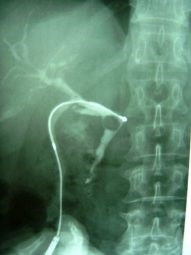

Extracción percutánea de cálculo de coledoco

Envíado por Dr. Carlos Miguel Zavaleta Consuegra